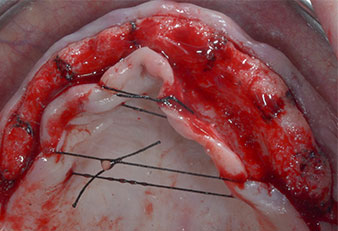

Compte tenu de la dureté relative de l’os (D2) à cet endroit, les sites recevant des implants de 10mm de long aux régions 11 et 21 ont été finalisés à l'aide d’une fraise de 4mm de diamètre, associée à un contre-angle chirurgical W&H WS-75 L, au moteur d'implantologie Implantmed de W&H ainsi qu’au module Osstell ISQ de W&H. En revanche, en raison de leur structure osseuse molle, les sites postérieurs ont été préparés en vue de l’obtention d’un diamètre final de 3mm à l'aide de l’insert Piezomed I3P. Les implants ont enfin été posés par voie transgingivale (Flap Less) pour obtenir l’ostéointégration dans un délai de trois mois (Figures 6-10). L'appareil existant a été maintenu sur quatre implants provisoires (Fig. 8).

Implant de 10mm au niveau du tissu

Fig. 6 : Un implant de 10mm au niveau du tissu est placé en région 21. L’implant en région 11 et les trois implants postérieurs gauches de 4mm sont déjà en place.